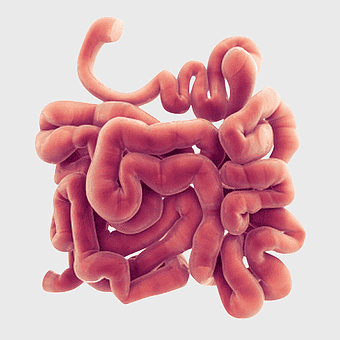

Crohn's disease illustration, gastrointestinal tract diagram, large intestine anatomy, digestive system cartoon, medical illustration, human anatomy study, chronic inflammatory bowel condition -

Gastrointestinal tract anatomy, Stomach health, Crohn's disease symptoms, Digestive system, Intestinal inflammation, Human anatomy illustration, Medical diagram -

digestive system diagram, gastrointestinal tract chart, human anatomy illustration, small intestine function, digestive process visualization, internal organ layout, metabolic system overview -

human digestive system illustration, gastrointestinal tract diagram, human body organ system, labeled digestive system, digestive anatomy chart, human internal organs, alimentary canal visualization -

Gastrointestinal tract diagram, Small intestine anatomy, Large intestine function, Apparato digerente illustration, Digestive system structure, Intestinal health, Human anatomy organs -

Gastrointestinal tract illustration, leaky gut syndrome symptoms, small intestine diagram, large intestine function, digestive system health, human anatomy chart, internal organ visualization -